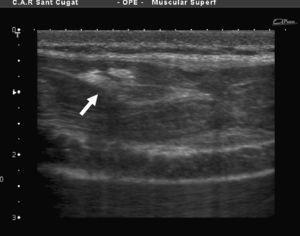

A pesar de los 7 días transcurridos, se observa una disrupción del correcto patrón fibrilar con sufusión hemática que invade la totalidad de la lesión y edema perilesional (figura 1, figura 2). El examen ecográfico también mostró una imagen fibrosa que, una vez interrogado el paciente, se concluyó que correspondía a una lesión antigua en el mismo vientre y asintomática en el momento de la consulta (figura 3).

Figura 2. Imagen ecográfica longitudinal de la misma ruptura.